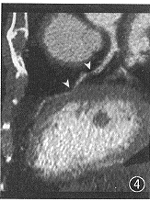

图4 与图3同一数据,曲面重组容易偏离血管中心线,造成酷似狭窄的伪像(箭头)

图7 与图6同一EBCT数据,曲面重组显示左主干(箭标)和前降支(箭头)的重度狭窄

MAR和CPR处理的正常冠状动脉EBCT造影图像分别示于图3、4,1例病变冠状动脉的造影、MAR、CPR图像分别示于图5~7。从中可以看出MAR具有以下特点(图3~12)。

1.MAR能保证曲截面准确贯穿血管轴线,从而保证反映血管最大径。而CPR靠徒手画曲线,不易掌握,也不能保证客观性,一旦画偏,则造成狭窄伪像。